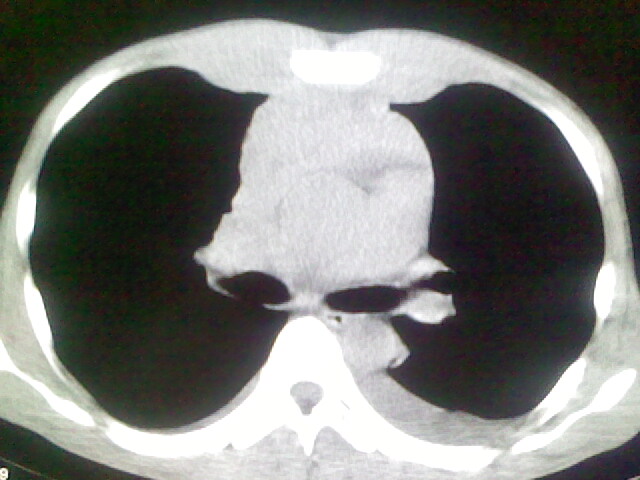

以下是引用杀毒软件在2008-9-3 6:11:00的发言:[br]侵袭性胸腺瘤------一般不侵到气管旁[br][br]考虑----纵隔淋巴瘤,心包及胸膜受累

以下是引用wzr在2008-9-3 5:30:00的发言:[br]侵袭性胸腺瘤

以下是引用随光逐影在2008-9-3 7:07:00的发言:[br]1)考虑淋巴瘤可能。2)双侧胸腔积液(以左侧为甚)。3)心包积液。